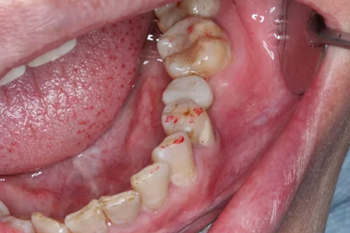

1.試戴臨時基臺,觀看咬頜位置并且記錄,將基臺在口外進行調(diào)磨。

4.醫(yī)生將臨時修復(fù)體與臨時基臺粘接后并且將其戴到患者口內(nèi)。

5.臨時修復(fù)體在患者口內(nèi)就位后的狀況。醫(yī)生將咬頜紙放入患者口內(nèi)將臨時修復(fù)體進行觀察調(diào)整。幾乎沒有經(jīng)歷調(diào)磨即可準確就位。